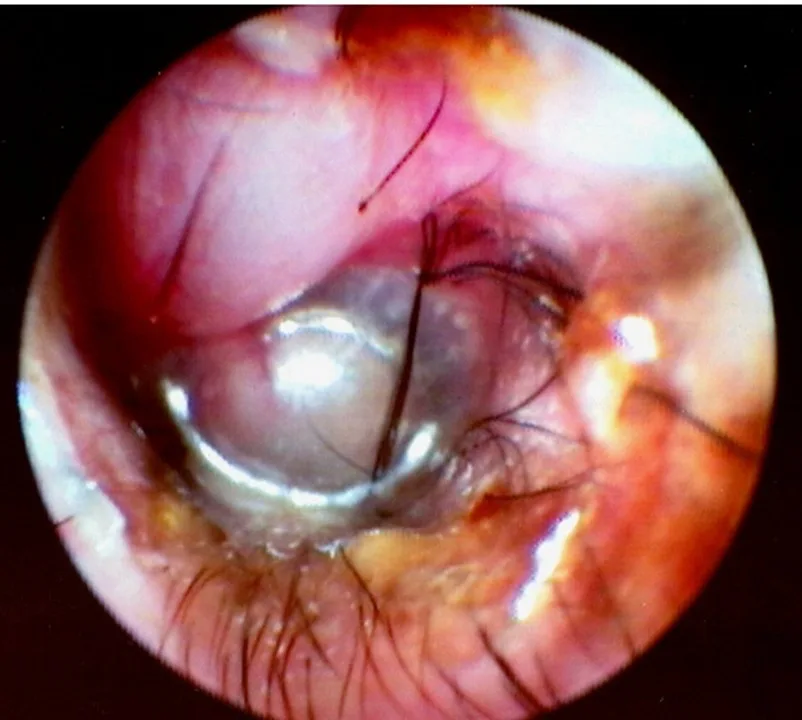

Visualization of fluids (eg, blood, pus, mucus, serum) behind the eardrum in the middle ear (Figure 2)

FIGURE 2 Left middle ear inflamed with exudate and blood behind eardrum (left). The normal right eardrum is shown for comparison (right).